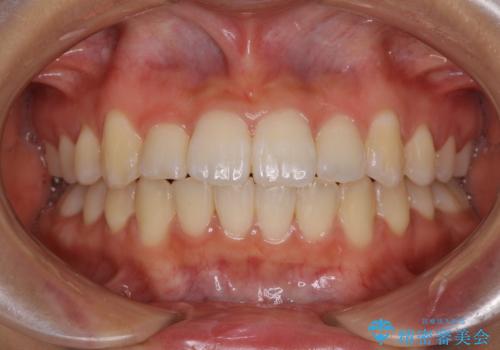

- 上下のデコボコと前歯のクロスバイトを改善したいとのことで来院された患者様です。

極力短期間で治療したいとのことで、ワイヤー装置による矯正治療を行うこととしました。

お住まいが遠方であったため、マウスピースによる矯正治療も提案しましたが、ご自身でのマウスピースの管理の面倒くささと、なるべく早く治療を終えたいとのことで、ワイヤー矯正を選択されました。